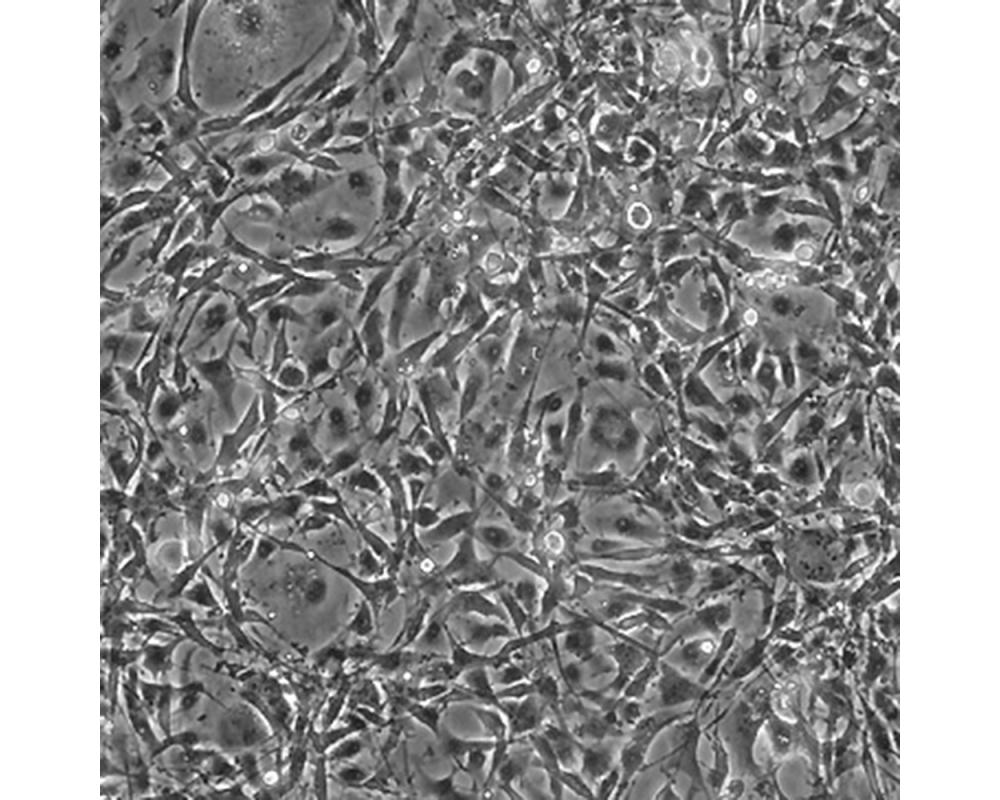

U-118 MG

中文名稱 人腦星形膠質(zhì)母細(xì)胞瘤

組織來源 星形膠質(zhì)母細(xì)胞瘤;男性

生長特性 adherent

形態(tài)特征 mixed

細(xì)胞描述 注意: 據(jù)報道來自不同個體的膠質(zhì)母細(xì)胞瘤細(xì)胞株U-118 MG (HTB-15) 和 U-138 MG (HTB-16)有著一致的VNTR和相近的STR模式。 U-118 MG 和 U-138 MG細(xì)胞遺傳學(xué)上很相似并有至少六個衍生標(biāo)記染色體。 這是1966年至1969年間J. Ponten和同事從惡性神經(jīng)膠質(zhì)瘤中構(gòu)建的細(xì)胞株中的一株(其它包括ATCC HTB-14和 ATCC HTB-16 and ATCC HTB-17)。 1987年用BM-Cycline培養(yǎng)6周去除了支原體污染。